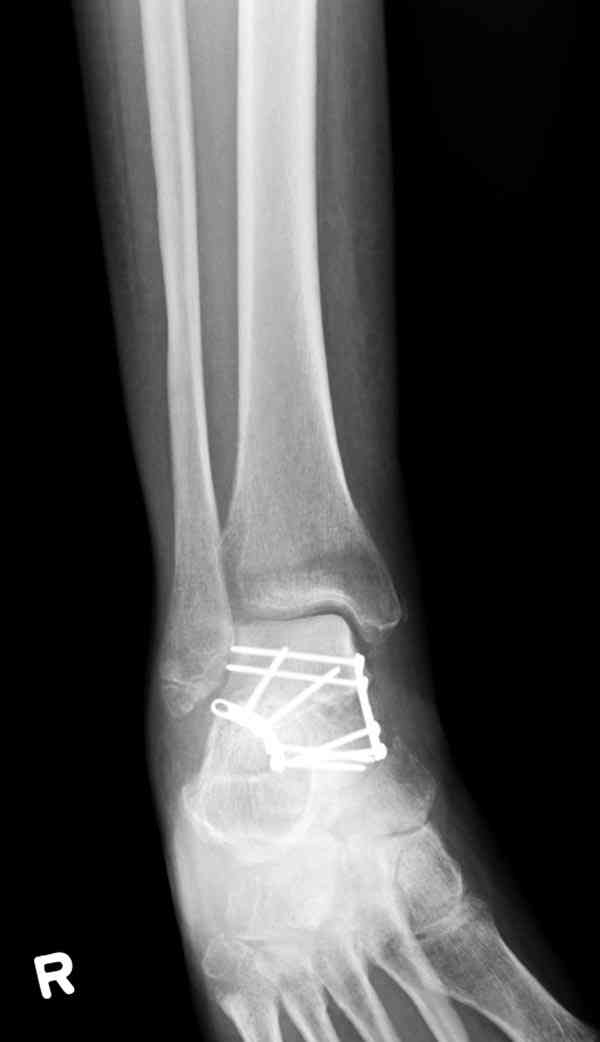

Случай с множественным оскольчатым переломом тарана оперированный из двойного доступа.

Через 14 мес.: